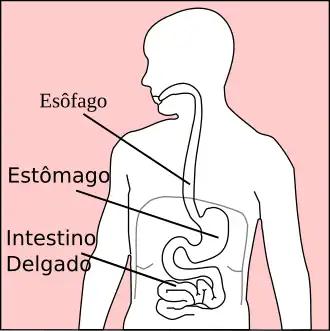

Fisiopatologia

O esôfago é um órgão oco em forma de tubo que une a faringe ao estômago. Sua principal função é, através de contrações peristálticas, realizar o transporte do alimento ingerido em direção ao estômago. O conteúdo do estômago é muito ácido, enquanto o do esôfago não é. Em função disso, o estômago possui um revestimento especial resistente à acidez. No entanto, o esôfago não possui um revestimento especial que seja capaz de resistir ao conteúdo ácido do estômago que se desloca até o esôfago quando a pessoa tem doença do refluxo gastroesofágico.